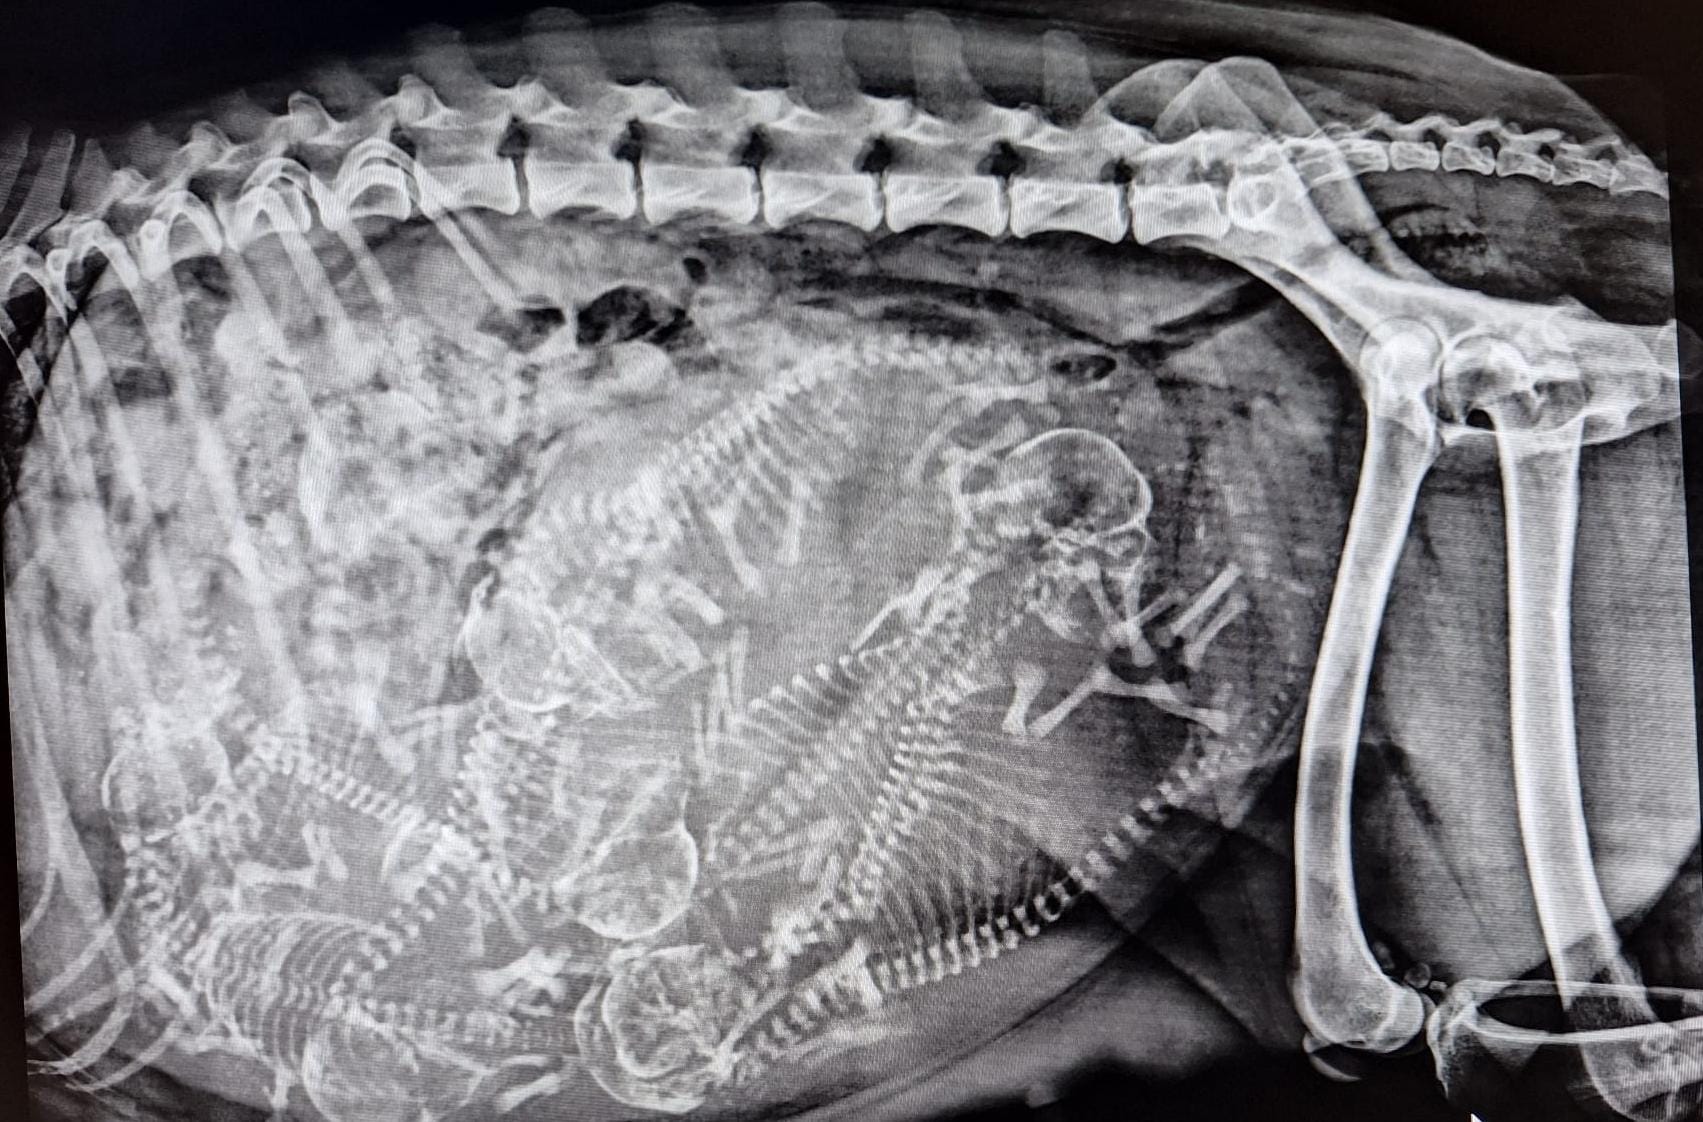

Geburt F Wurf